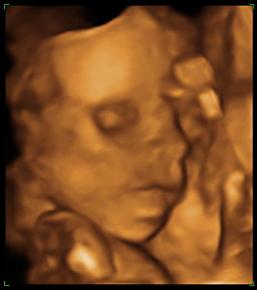

babalak a 22. héten

Dávid